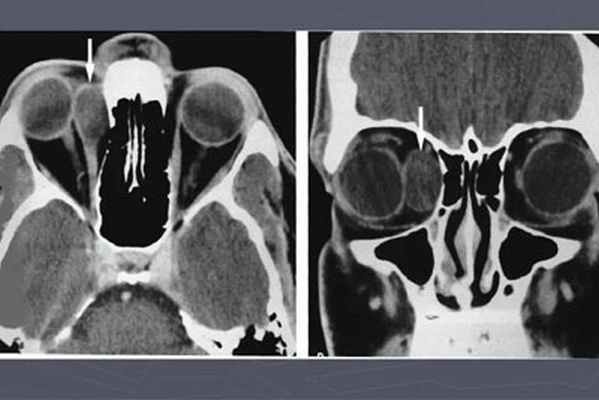

Так как рост новообразования происходит постоянно и может травмировать окружающие ткани, необходимо обратиться к врачу за консультацией сразу после обнаружения. Перед лечением дермоидных кист важно сделать грамотную диагностику и дифференцировать их от других новообразований. Применяется инструментальное и лабораторное исследование.

Для дифференциации диагноза хирург может назначить УЗИ новообразования, КТ места локализации кисты, рентгенографию области новообразования.

Дермоидная киста относится к разновидности фиброэпителиальных образований, имеющих стенки из соединительной ткани. Дермоидная киста обычно окружена капсулой, имеющей овальную или неправильную форму, и со временем может достигать величины крупной горошины или грецкого ореха. Дермоидная киста глаза может состоять как из одной, так и из нескольких полостей, заполненных сальной массой с примесью ороговевших кожных чешуек или волос. В зависимости от характера содержимого киста может быть плотной или мягкой.

Дермоидную кисту обычно выявляют в раннем возрасте, так как она представляет собой округлый или вытянутой формы «шарик», который располагается под кожей. При ощупывании кисты болезненных ощущений у пациента не возникает. Диагностика дермоидной кисты не вызывает сложностей, но в некоторых случаях необходимо проводить дифференциальную диагностику. Если киста локализуется в области корня носа, то ее дифференцируют от мозговой грыжи. В том случае, когда дермоидная киста располагается на шее, то проводится дифференциация ее от врожденных срединных и боковых кист. Если киста локализуется в яичнике, то для диагностики применяют ультразвуковое исследование.